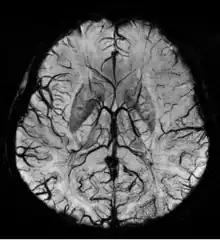

Susceptibility weighted imaging (SWI), originally called BOLD venographic imaging, is an MRI sequence that is exquisitely sensitive to venous blood, hemorrhage and iron storage. SWI uses a fully flow compensated, long echo, gradient recalled echo (GRE) pulse sequence to acquire images. This method exploits the susceptibility differences between tissues and uses the phase image to detect these differences. The magnitude and phase data are combined to produce an enhanced contrast magnitude image. The imaging of venous blood with SWI is a blood-oxygen-level dependent (BOLD) technique which is why it was (and is sometimes still) referred to as BOLD venography. Due to its sensitivity to venous blood SWI is commonly used in traumatic brain injuries (TBI) and for high resolution brain venographies but has many other clinical applications. SWI is offered as a clinical package by Philips and Siemens but can be run on any manufacturer's machine at field strengths of 1.0 T, 1.5 T, 3.0 T and higher.

SWI uses a fully velocity compensated, RF spoiled, high-resolution, 3D gradient recalled echo (GRE) scan. Both the magnitude and phase images are saved, and the phase image is high pass (HP) filtered to remove unwanted artifacts. The magnitude image is then combined with the phase image to create an enhanced contrast magnitude image referred to as the susceptibility weighted (SW) image. It is also common to create minimum intensity projections (mIP) over 8 to 10 mm to better visualize vein connectivity. In this way four sets of images are generated, the original magnitude, HP filtered phase, susceptibility weighted, and mIPs over the susceptibility weighted images.

The susceptibility weighted image is created by combining the magnitude and filtered phase images. A mask is created from the phase image by mapping all values above 0 radians to be 1 and linearly mapping values from -π to 0 radians to range from 0 to 1, respectively. Alternatively, a power function (typically 4th degree) can be used instead of a linear mapping from -π to 0 to increase the effect of the mask. The magnitude image is then multiplied by this mask. In this way phase values above 0 radians have no effect and phase values below 0 radians darken the magnitude image. This increases the contrast in the magnitude image for objects with low phase values such as veins, iron, and hemorrhage.